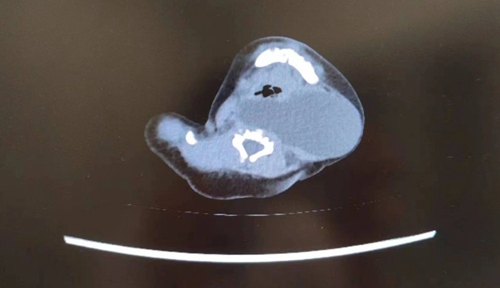

随着孕周增加,胎儿颈部包块逐渐增大。孕39周时,超声提示囊肿增大至42*39.9mm,为确保母婴安全,胎儿医学中心、产科专家经过分析决定为孕妇实行剖宫产。医护团队反复评估和讨论,制定了周密的手术计划,芳芳顺利分娩一名女婴。宝宝出生后,专家检查发现囊肿位于患儿咽后及左侧动脉间隙,可能流脓、感染,且肿物越长越大,可能压迫宝宝气管,手术风险和麻醉风险都将进一步提升,必须及早手术。

时间紧迫,越早手术效果越好。宝宝出生第2天,救治团队为患儿进行全麻下置管引流+超声引导经皮硬化术,引流脓液约80ml,成功清除囊肿。